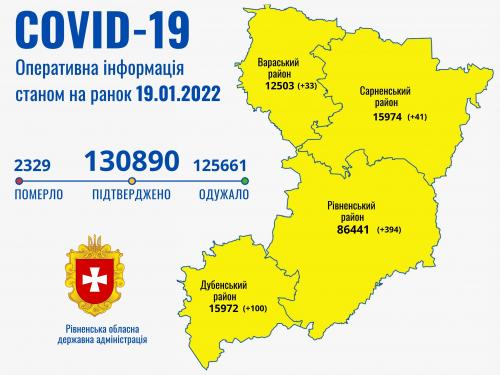

Коронавірус повертається: як стрімко зростає кількість хворих на Рівненщині (ВІДЕО)

Пів тисячі - у важкому стані, 9 жителів Рівненщини померли за добу від коронавірусу